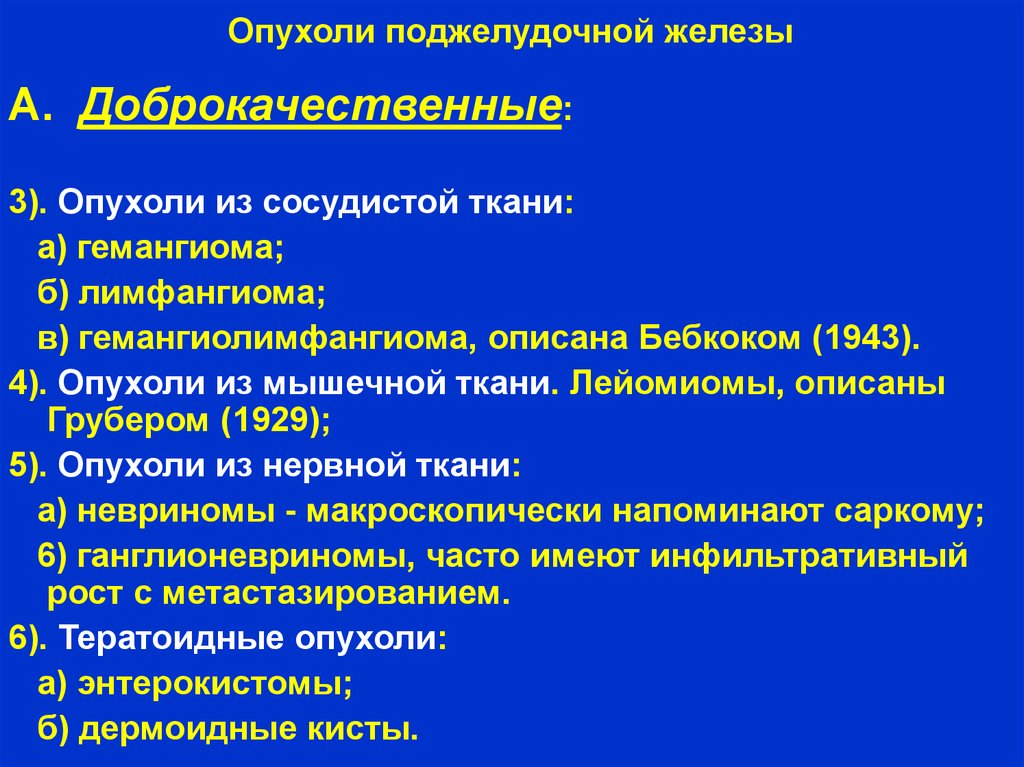

Классификация опухолей. Классификация новообразований. Классификация опухолей по воз. Классификация воз опухолей костей. Опухоли головки поджелудочной железы классификация. Доброкачественная опухоль поджелудочной. Доброкачественная опухоль поджелудочной железы. Гистологическая классификация опухолей поджелудочной железы.

Опухоли головки поджелудочной железы классификация. Доброкачественная опухоль поджелудочной. Доброкачественная опухоль поджелудочной железы. Гистологическая классификация опухолей поджелудочной железы. Магнитно-резонансная томография. Исследования магнитно-резонансной томографии:. Обследование на томографе. Мрт.